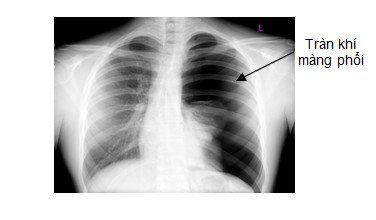

Vì sao có khí trong màng phổi? Chẩn đoán trên X quang có chính xác không?

Khi tràn dịch màng phổi dịch tiết, khoang màng phổi có dịch sẽ gây nên nên hiện tượng dày màng phổi với hình ảnh rõ nét trên phim. Do vậy, X quang là xét nghiệm cận lâm sàng quan trọng nhất trong chẩn đoán bệnh lý phổi.